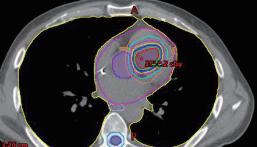

在一位曾經接受過 SBRT 的病患的心肌切片中 ( 圖 二 ),可以看見出現了部分的纖維化。比較特別的是, 這位接受過 SBRT 的心肌沒有出現接受到一般放射線 的心肌常見的急性心肌壞死、出血或是發炎,由此可 見在初次接受 SBRT 的幾週內並不會產生對心臟多餘 的傷害 4 。 在效果上,ENCORE-VT 臨床試驗指出接受過 SBRT 的 19 位病人發生的 VT 以及使用 ICD shock therapy 的次數大幅下降,的次數大幅下降,6 個月以 及 12 個月的存活率分別可達 89% 和 72%,此外整體 ablation 之外,還有較少去施行的外科處置,以及本 篇要探討的全身立體定位放射治療 (stereotactic body radiation therapy, SBRT)。 何謂 SBRT ?顧名思義就是使用高精準度的放射 線去照射我們所標定的目標處,之前為人所知的是用 在不適合開刀的早期肺癌。其原理如圖一所示,人體 細胞在接受到放射線之後,不管是放射線本身還是受 到放射線而裂解出的氫氧自由基都會對 DNA 造成傷 害,在受到傷害之後細胞可能會死亡、DNA 修復或是 纖維化 3 。 ( 圖ㄧ ) ( 圖二 ) 的生活品質也大幅提升 5。在安全性部分,SBRT 這樣 的放射線還是可能對冠狀動脈、心臟傳導系統、瓣膜、 心肌以及心包膜造成後續影響,可能會發生心包膜炎 或是心包膜積液。而更長期的安全性報告則需要更多 的後續研究來證實。 台大醫院的流程是先用核磁共振、電腦斷層以及 心臟電生理定位出 substrate 的位置,接著由放射腫瘤 科,放射診斷科以及電生理科醫師共同擬定 SBRT 計 畫,最後施行放射線治療。以一個病人為例,一位 47 歲的男性,有擴張型心肌病變 (dilated cardiomyopathy) 10 NO.047

中華民國心律醫學會‧ Taiwan Heart Rhythm Soclety ‧中華民國 111 年 9 月出刊 ( 圖三 ) ( 圖四 ) ( 圖五 ) 和原發於右心室流出道 (right ventricular outflow tract, RVOT) 的 refractory VT。定位的位置是在 RVOT。 SBRT 進行的計畫顯示腫瘤體積 (gross target volume, GTV) 有 4.6 ml,而計畫靶體積 (planning target volume, PTV ) 有 14.4 ml,如 ( 圖三 ) 至 ( 圖五 ) 所表示。SBRT 進行時間為 11.9 秒,由 6 個共平面以及 4 個非共平面的 放射源進行照射,如 ( 圖六 ) 所示。而在進行完 SBRT 後, 病人 VT 的次數以及持續時間皆有顯著的下降 ( 圖七 )。 ( 圖六 ) 綜合上述,在 refractory VT 的病人使用 SBRT 可 以達成不錯的短期效果,顯著降低 VT 的次數和持續 時間,另外安全性的部分至少短期內不會對其他心肌 造成額外的傷害。雖然說長期的安全性與副作用還是 未知,但 SBRT 確實是幫 refractory VT 找到了新的治 療道路。 Reference: 1. Di Biase L, Burkhardt JD, Lakkireddy D, Carbucicchio C, Mohanty S, Mohanty P, Trivedi C, Santangeli P, Bai R, Forleo G, Horton R, Bailey S, Sanchez J, AlAhmad A, Hranitzky P, Gallinghouse GJ, Pelargonio G, Hongo RH, Beheiry S, Hao SC, Reddy M, Rossillo A, Themistoclakis S, Dello Russo A, Casella M, Tondo C, Natale A. Ablation of Stable VTs Versus Substrate Ablation in Ischemic Cardiomyopathy: The VISTA Randomized Multicenter Trial. J Am Coll Cardiol. 2015;66:2872–2882. 2. Tokuda M, Kojodjojo P, Tung S, Tedrow UB, Nof E, Inada K, Koplan BA, Michaud GF, John RM, Epstein ( 圖七 ) 11NO.047